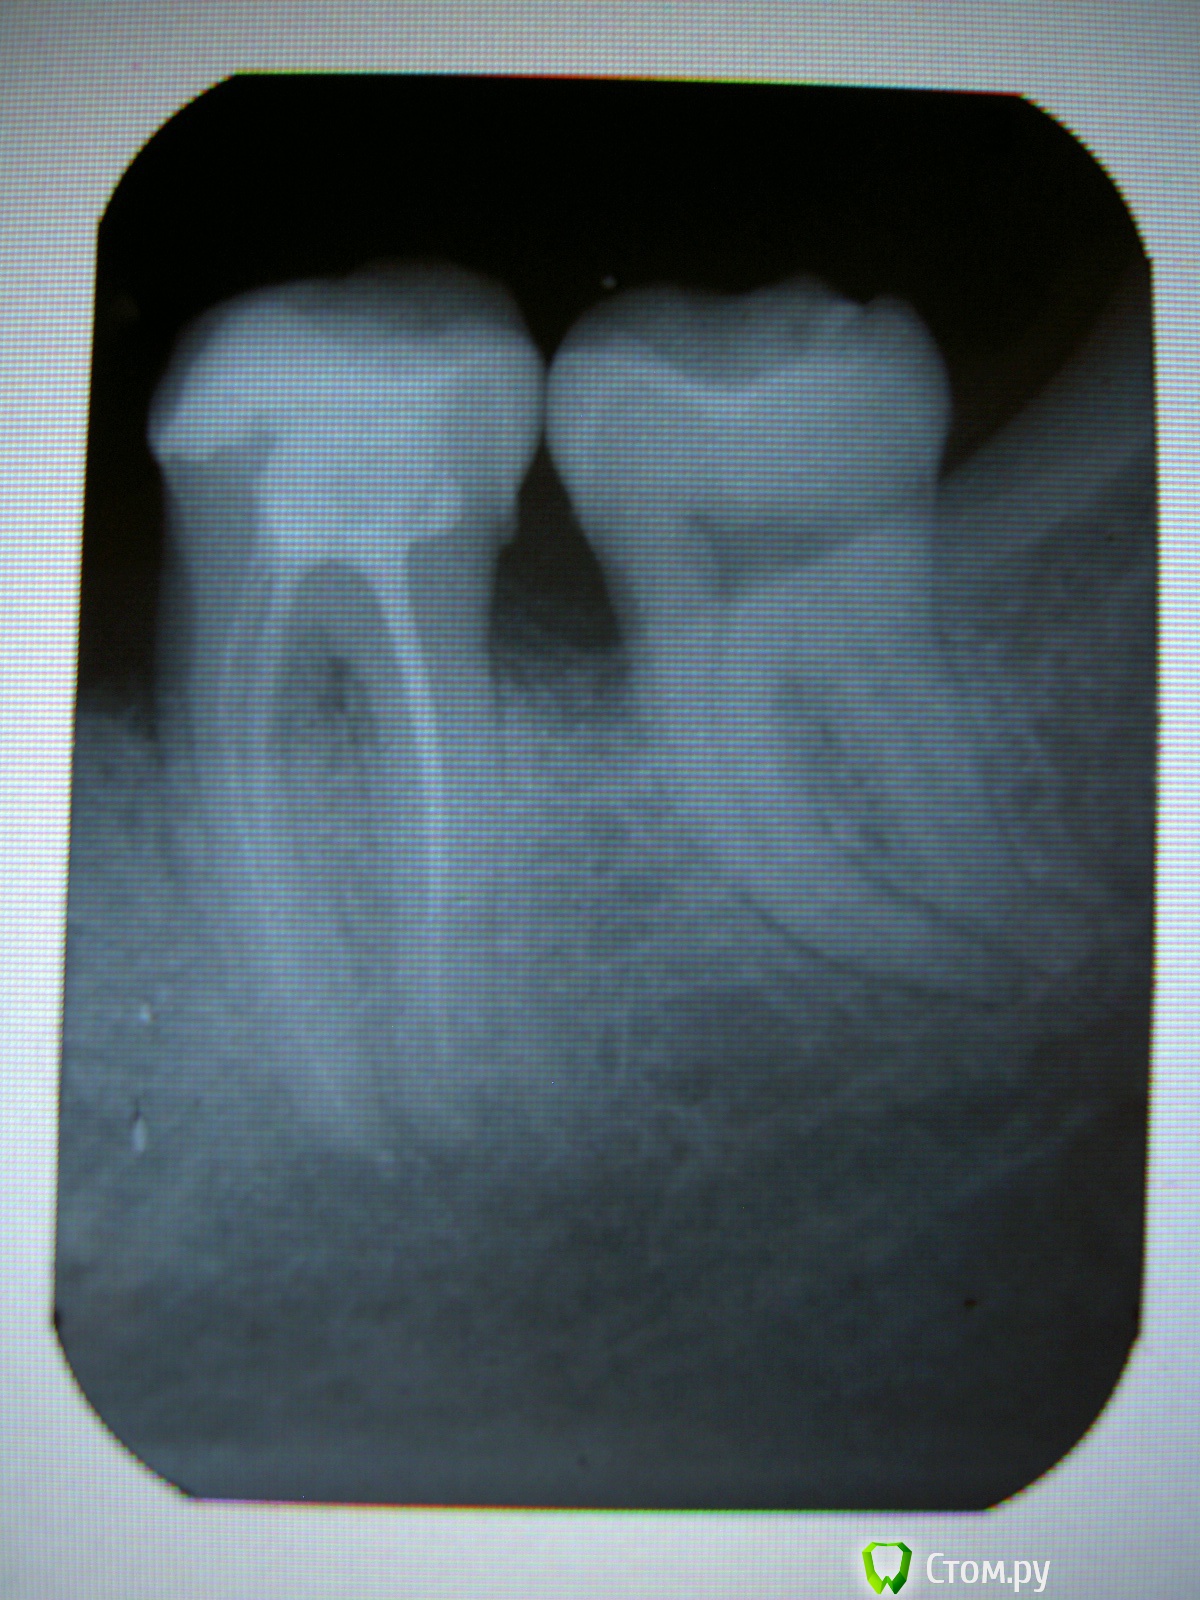

KOV Опубликовано 23 января, 2014 Автор Поделиться Опубликовано 23 января, 2014 Уважаемые врачи!Можно ли подробнее описать снимок 47/48? Видно ли на нём - ЧТО сделано неправильно? Необоснованный аргумент, что нужно переделать - врачами в клинике не принимается.И может ли разрежение у корня 48-го быть источником боли?Заранее спасибо. Ссылка на комментарий

ромашечка Опубликовано 23 января, 2014 Поделиться Опубликовано 23 января, 2014 Видно , что каналы залечены не до верхушки и достаточно" редко, тонко". Посмотрите на снимки в разделе для врачей. И увидите , как выглядят правильно залеченные каналы. Ваш основной аргумент- должен быть Постоянная ноющая боль мешает полноценной жизни. Все мысли ежеминутно направлены в одно русло... А так какболь возникла после лечения- то очень большая вероятность , что болит именно этот зуб. Учитывая снимок- тем более. 48 мне видится интактным(здоровым), но может я ошибаюсь . Вы где лечились? Платно , бесплатно? Как долго длилось лечение каналов? Я бы , наверное, искала другого врача. Ссылка на комментарий

KOV Опубликовано 23 января, 2014 Автор Поделиться Опубликовано 23 января, 2014 Прошу прощения. Не получается сегодня вставить цитату в ответ.Для Ромашечка.Лечила в платном отделении муниципальной поликлиники. Каналы, вроде, и не лечили. 13 декабря поставили пломбу на 47 и 48 зубы. На 48-м пломба совсем маленькая. 24 декабря, при повторном обращении, пломбу с 47-го сняли, нервы удалили, каналы запломбировали, поставили пломбу и всё на этом.Вот и мне, показалось, что каналы тонко запломбированы. Врачу сказала об этом, на что мне ответили, что справа (на снимке) , там, где канал более ярко выражен, накладывается изображение одного канала на другой и, поэтому, такой яркий белый цвет, а слева, где видно два канала , всё замечательно. Хотя, мне кажется, что он как-то подозрительно ветвист...не расширен, что ли...Вот, только подозрения свои грамотно изложить не получается(((Больше всего смутило, что поход к другому специалисту, принёс тот же результат. Этому врачу нет оснований не доверять. В моём случае им были вылечены два достаточно проблемных зуба. Вылечены замечательно. Но, и он думает на 48-й. Можно было бы попробовать его депульпировать, но, может и не получиться пройти каналы, тогда на удаление. Слишком рискованно. Вдруг, всё же 47-й болит. Ссылка на комментарий

KOV Опубликовано 23 января, 2014 Автор Поделиться Опубликовано 23 января, 2014 Ромашечка, я, тоже, думаю на 47-й. Пробовала стучать, холодную воду, горячий металл прикладывала. Особенно ничего не беспокоит. Если, только, при постукивании неприятные ощущения на 47-м, но в месте рядом с 48-м. Боль какая-то ноющая, как будто изнутри идёт, кажется, что как будто внутри зуба воспаление.Коффердама не было, прибора, тоже, хлорки, также))) В кресле сидела минут 30. Снимок сделали после пломбировки каналов, после чего ещё немного допломбировали, но, снимок больше не делали. Поликлиника муниципальная, но, отделение платное. В принципе, отличие, лишь в более комфортных условиях и высоких расценках. Премудростей о которых читаю на форуме и в помине нет)).P.S. Врачей оценивать не бралась. Зачем мне это. Разница в ощущении после лечения. Один бился с зубом 3 часа и всё ОК. Второй, зачем-то, снял всю эмаль с зуба и теперь ощущение, что по зубу давно не проходились зубной щёткой. После 3-го зуб болит полтора месяца. Оценка субъективная, но дискомфорт объективный.Прошу прощения за оффтоп. Ссылка на комментарий